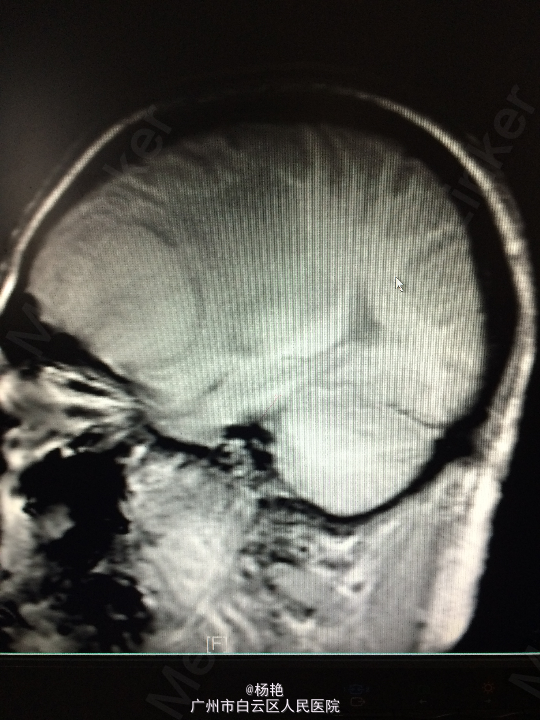

主诉:反复头痛2年加重1周 病史:患者诉两年前无明显诱因反复出现头晕头痛不适,近一周来症状加重,无恶心呕吐、无行走不稳、肢体乏力、意识障碍等。遂至当地医院诊治,行头颅CT、MR检查均提示颅内占位,良性可能性大,考虑脑膜瘤。今患者为求进一步治疗而入我院。

查体:神经系统查体未见明显异常 辅助检查:头颅MR提示:左侧额叶区域较大类圆形肿物,多考虑脑膜瘤可能;大脑前动脉及中动脉受压,中线偏移。

诊断:左额叶脑膜瘤 处理:在静脉全麻下行左侧额底脑膜瘤切除术,术后病理提示:脑膜瘤